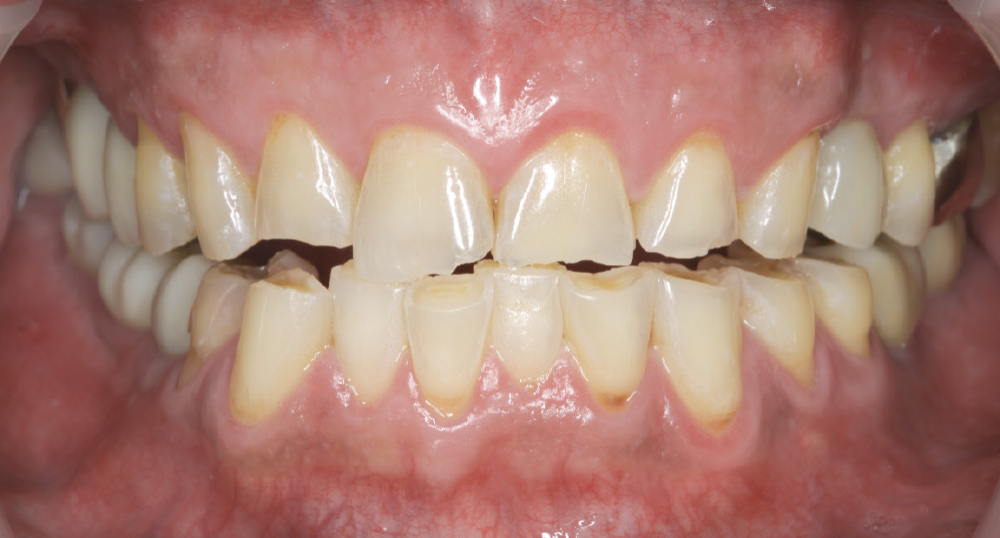

Assess Parafunctional Habits

Assess Parafunctional Habits. Evaluating signs of parafunctional habits, including bruxism or clenching, provides critical information that influences material selection and occlusal design. Share these findings with the laboratory to inform restoration fabrication decisions, ensuring the final prosthesis is designed to minimize harmful excursive forces during function.

Implant post in socket

Finished Implant Restoration